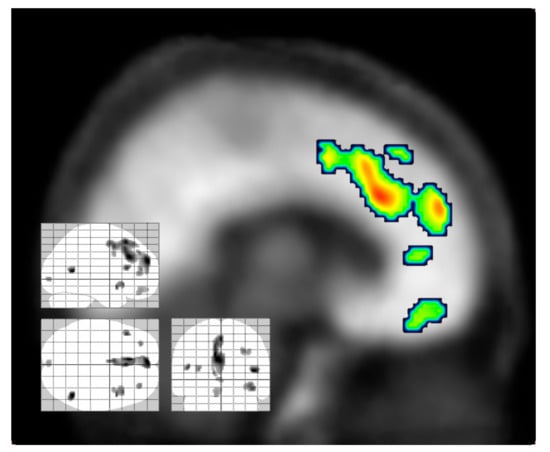

- Carhart-Harris, R.L.; Muthukumaraswamy, S.; Roseman, L.; Kaelen, M.; Droog, W.; Murphy, K.; Tagliazucchi, E.; Schenberg, E.E.; Nest, T.; Orban, C.; et al. Neural correlates of the LSD experience revealed by multimodal neuroimaging. Proc. Natl. Acad. Sci. USA 2016, 113, 4853–4858. [Google Scholar] [CrossRef]

- Carhart-Harris, R.L.; Erritzoe, D.; Williams, T.; Stone, J.M.; Reed, L.J.; Colasanti, A.; Tyacke, R.J.; Leech, R.; Malizia, A.L.; Murphy, K.; et al. Neural correlates of the psychedelic state as determined by fMRI studies with psilocybin. Proc. Natl. Acad. Sci. USA 2012, 109, 2138–2143. [Google Scholar] [CrossRef] [PubMed]